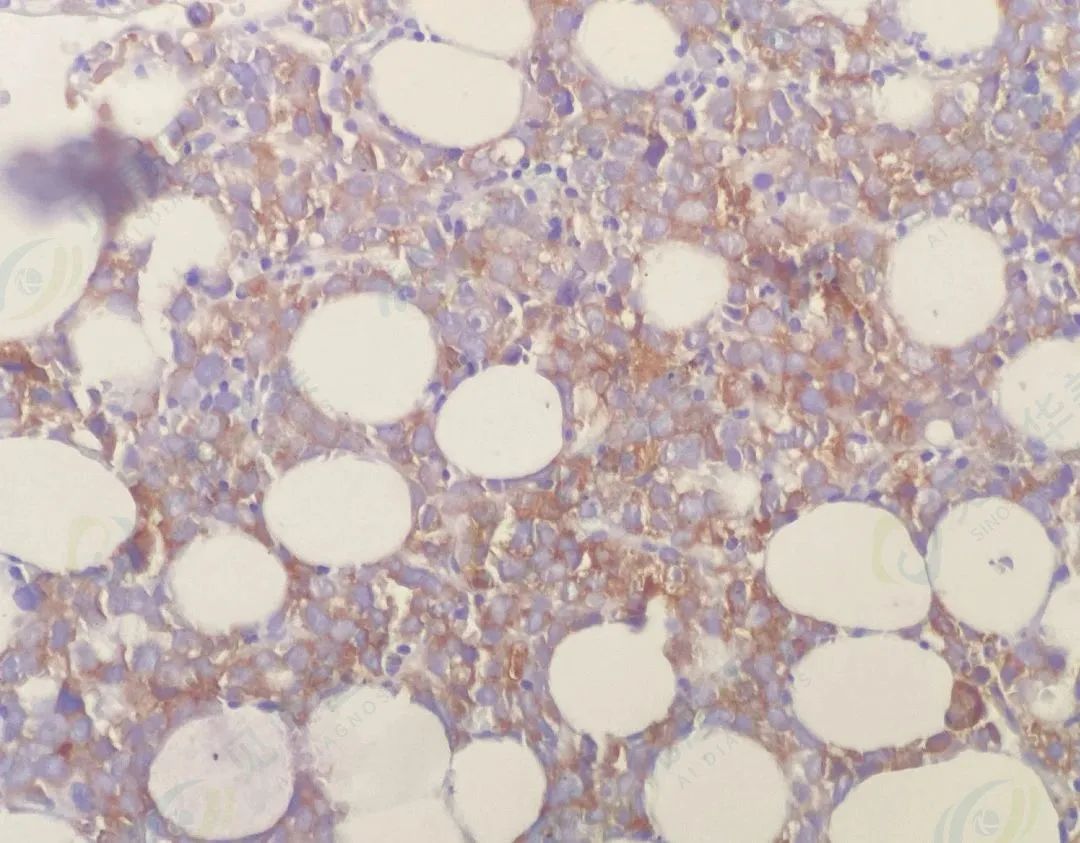

加做免疫组化

(异常细胞需鉴别原始红细胞、转移癌细胞及淋巴瘤细胞,病理免疫组化排除了转移癌、淋巴瘤,CD43+、E-cad+、CD71+支持为红系,骨髓细胞形态学示片尾区域红系超过80%,原始红为主,考虑AML-M6)